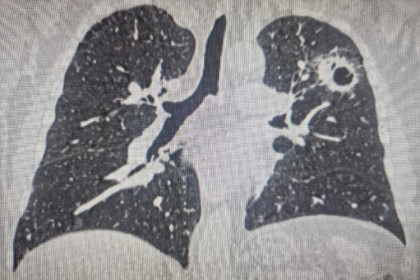

«У пациентки была затруднена речь, нарушена координация движений, что сразу наводило на мысль о проблемах с мозжечком. Подозрение подтвердили снимки магнитно-резонансной томографии, на которых видно объёмное новообразование. Решено было госпитализировать женщину и утром прооперировать, потому что в таких ситуациях опасно отпускать человека домой даже на несколько часов», – комментирует ситуацию нейрохирург Ильяс Кылданов, руководивший проведением операции.

Обычно хирургические вмешательства по поводу опухолей головного мозга проводятся в плановом порядке, что позволяет тщательно подготовиться к процедуре. Однако в данном случае экстренная госпитализация и оперативное вмешательство были продиктованы критическим состоянием пациентки. Новообразование перекрывало ликворопроводящие пути. Циркуляция ликвора (спинномозговой жидкости) в системе головного и спинного мозга является жизненно важной для нормального функционирования центральной нервной системы, обеспечивая движение, речь, память и когнитивные функции. Нарушение оттока ликвора приводит к повышению внутричерепного давления, сдавлению мозговых структур и, в критических случаях, к летальному исходу.